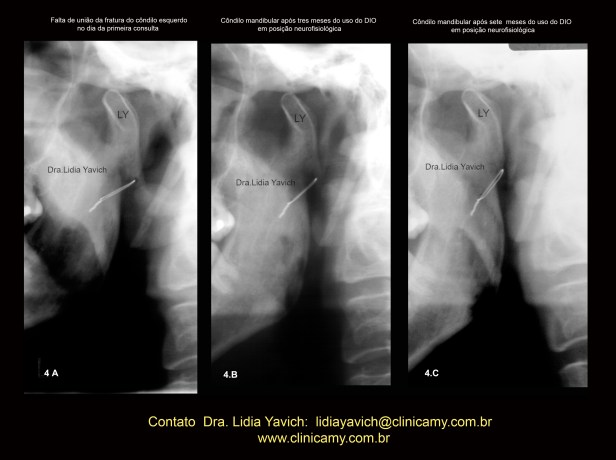

Imagem comparativa do côndilo mandibular esquerdo na primeira radiografia panorâmica do paciente no dia da consulta (4A).

Segunda radiografia panorâmica três meses após (4B)

Terceira radiografia panorâmica (4C) quatro meses após o segundo controle mostrando a melhora da posição do côndilo mandibular e a união do osso.

OBSERVAR A VERTICALIZAÇÃO DO FIO METÁLICO DA CIRURGIA

INVERSÃO DA COR da imagem comparativa do côndilo mandibular esquerdo na primeira radiografia panorâmica do paciente no dia da consulta (4A), segunda radiografia panorâmica três meses após (4B) e terceira radiografia panorâmica (4C) quatro meses após o segundo controle mostrando a melhora da posição do côndilo mandibular e a união do osso.

OBSERVAR A VERTICALIZAÇÃO DO FIO METÁLICO DA CIRURGIA.

Imagem comparativa do côndilo mandibular esquerdo na primeira radiografia panorâmica do paciente no dia da consulta (4A), segunda radiografia panorâmica três meses após (4B) e terceira radiografia panorâmica (4C) quatro meses após o segundo controle mostrando a melhora da posição do côndilo mandibular e a união do osso.